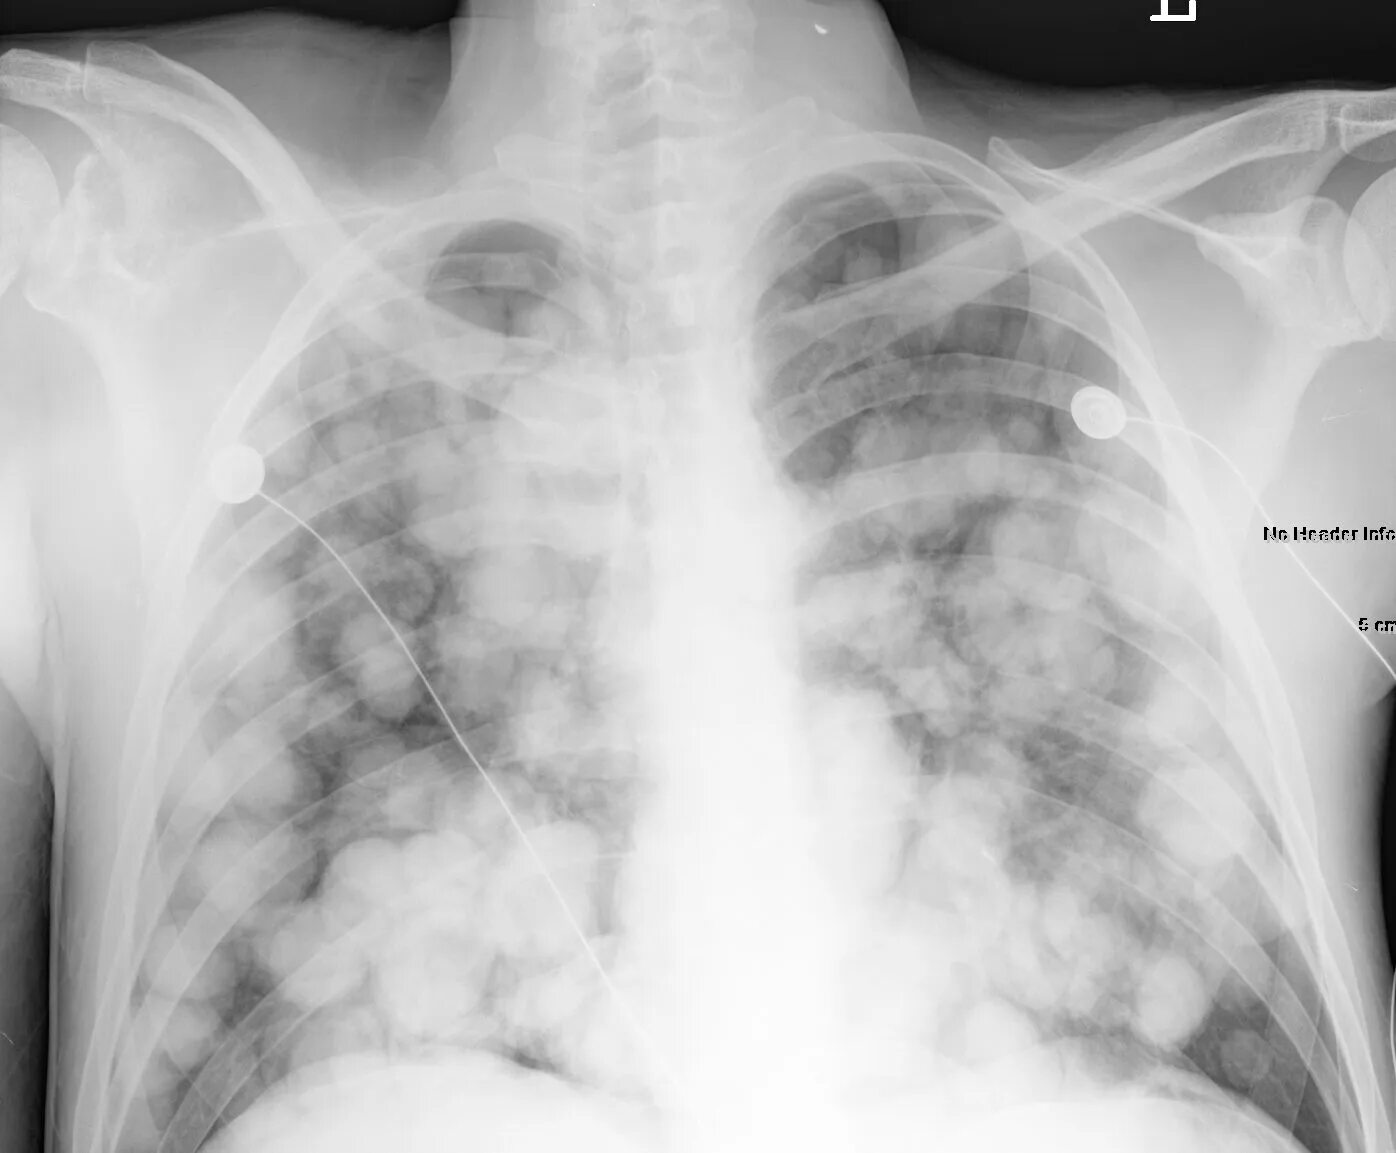

Сильная мокрота в легких